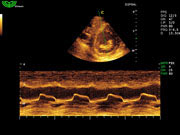

Система поддерживает СFM-режим, PW-режим, CW-режим, режим направленного энергетического потока, режим Color-M, панорамный режим, ECG, DICOM 3.0 и универсальные пакеты программ для кардиологии, сосудистого исследования и акушерства.

Режимы изображения: B, 2B, B/M, B/BC, CFM, PW, HPRF, PD, направленный PD, CW, режим Color M.

D3P64L 3.0МГц, фазированная решетка.

2.0МГц – 4.4МГц. Применения: кардиология, брюшная полость, акушерство. |